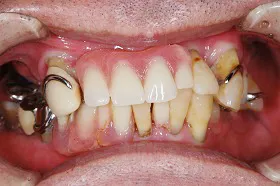

重度の歯槽膿漏のケース

■治療前

■治療後